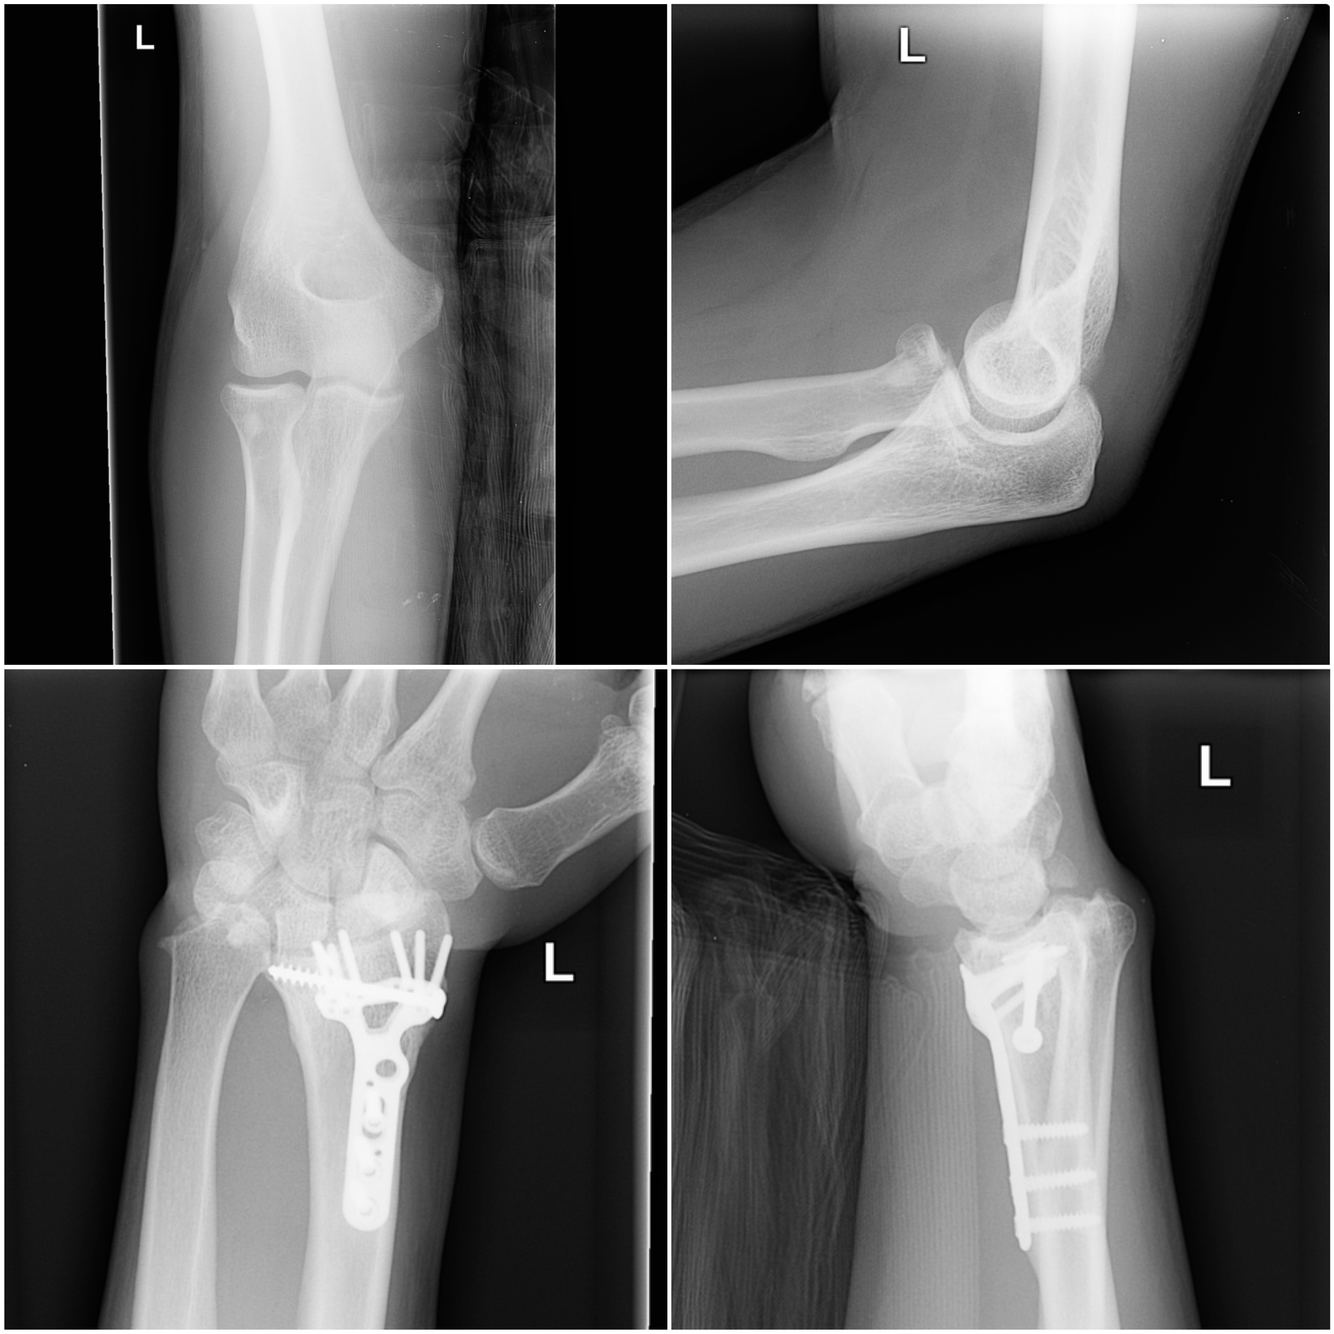

Essex-Lopresti fracture-dislocation

Intra-articular radial head fracture with a large joint effusion (sail sign), with dorsal dislocation of the ulna at the distal radioulnar joint (DRUJ).

Dr Henry Knipe◉◈ and Assoc Prof Frank Gaillard◉◈ et al.

Essex-Lopresti fracture-dislocation is characterised by a fracture of the radial head, dislocation of the distal radioulnar joint and rupture of the antebrachial interosseous membrane 3.

Epidemiology

As little as 20% of Essex-Lopresti fracture-dislocations are recognised at the time of initial presentation 6.

Clinical presentation

The injury occurs due to the compressive force of trauma transmitted down the forearm through the proximal and distal radioulnar joints and the interosseous membrane 3,4. This usually occurs from a fall or high energy trauma with the elbow extended 4. As a result, there is axial and longitudinal loading that causes pain and instability. The distal radioulnar joint injury may be missed, leading to permanent wrist pain and stiffness or instability. Radiocapitellar impingement due to longitudinal instability may cause lateral elbow pain 4.

Classification

The proposed classification of Essex-Lopresti fracture-dislocation is based on the severity of radial head fracture 5.

type I: large fragments

type II: comminuted

type III: chronic injury with proximal migration of the radial head

Pathology

Rupture of the interosseous membrane results in perturbed transmission of force from the radius to the ulna 7. If not recognised acutely, chronic instability and proximal migration of the radius results in ulna abutment with increased force transmission across the ulnocarpal joint 4.

Radiographic features

Initial radiographs may be unremarkable for Essex-Lopresti fracture-dislocations 6.

Treatment and prognosis

There have been historically poor outcomes in the treatment of longitudinal forearm instability which is particularly complex in the chronic setting 3. The low incidence, late presentations and heterogeneity in study samples presented in the literature preclude researchers reaching safe conclusions and planning of clinical studies 3. A recent study found that radial head replacement with the reconstruction of the interosseous membranes and central band restores radioulnar displacement and ulna forces to near normal 3.

The proposed treatment may be based on the classification type 5.

type I: open reduction and internal fixation

type II: radial head excision and prosthetic replacement

type III: radial head replacement and ulnar shortening osteotomy

History and etymology

It is named after Peter Gordon Essex-Lopresti (1916-1951), a trauma surgeon at Birmingham accident hospital, England 2.